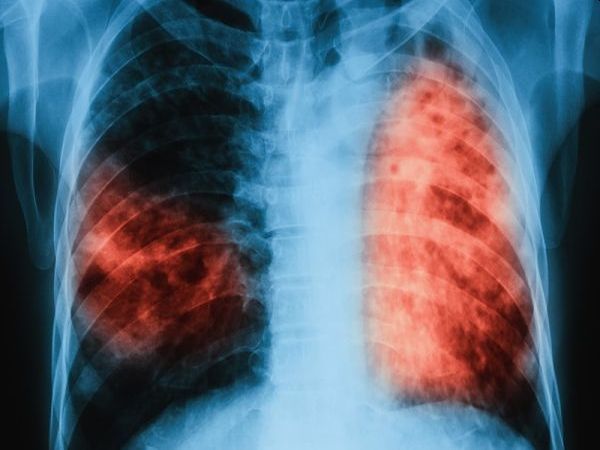

Туберкулозата е най-смъртоносната инфекциозна болест в света, която засяга най-често белите дробове. Тя е лечима и предотвратима болест при ранна диагностика и навременно лечение.